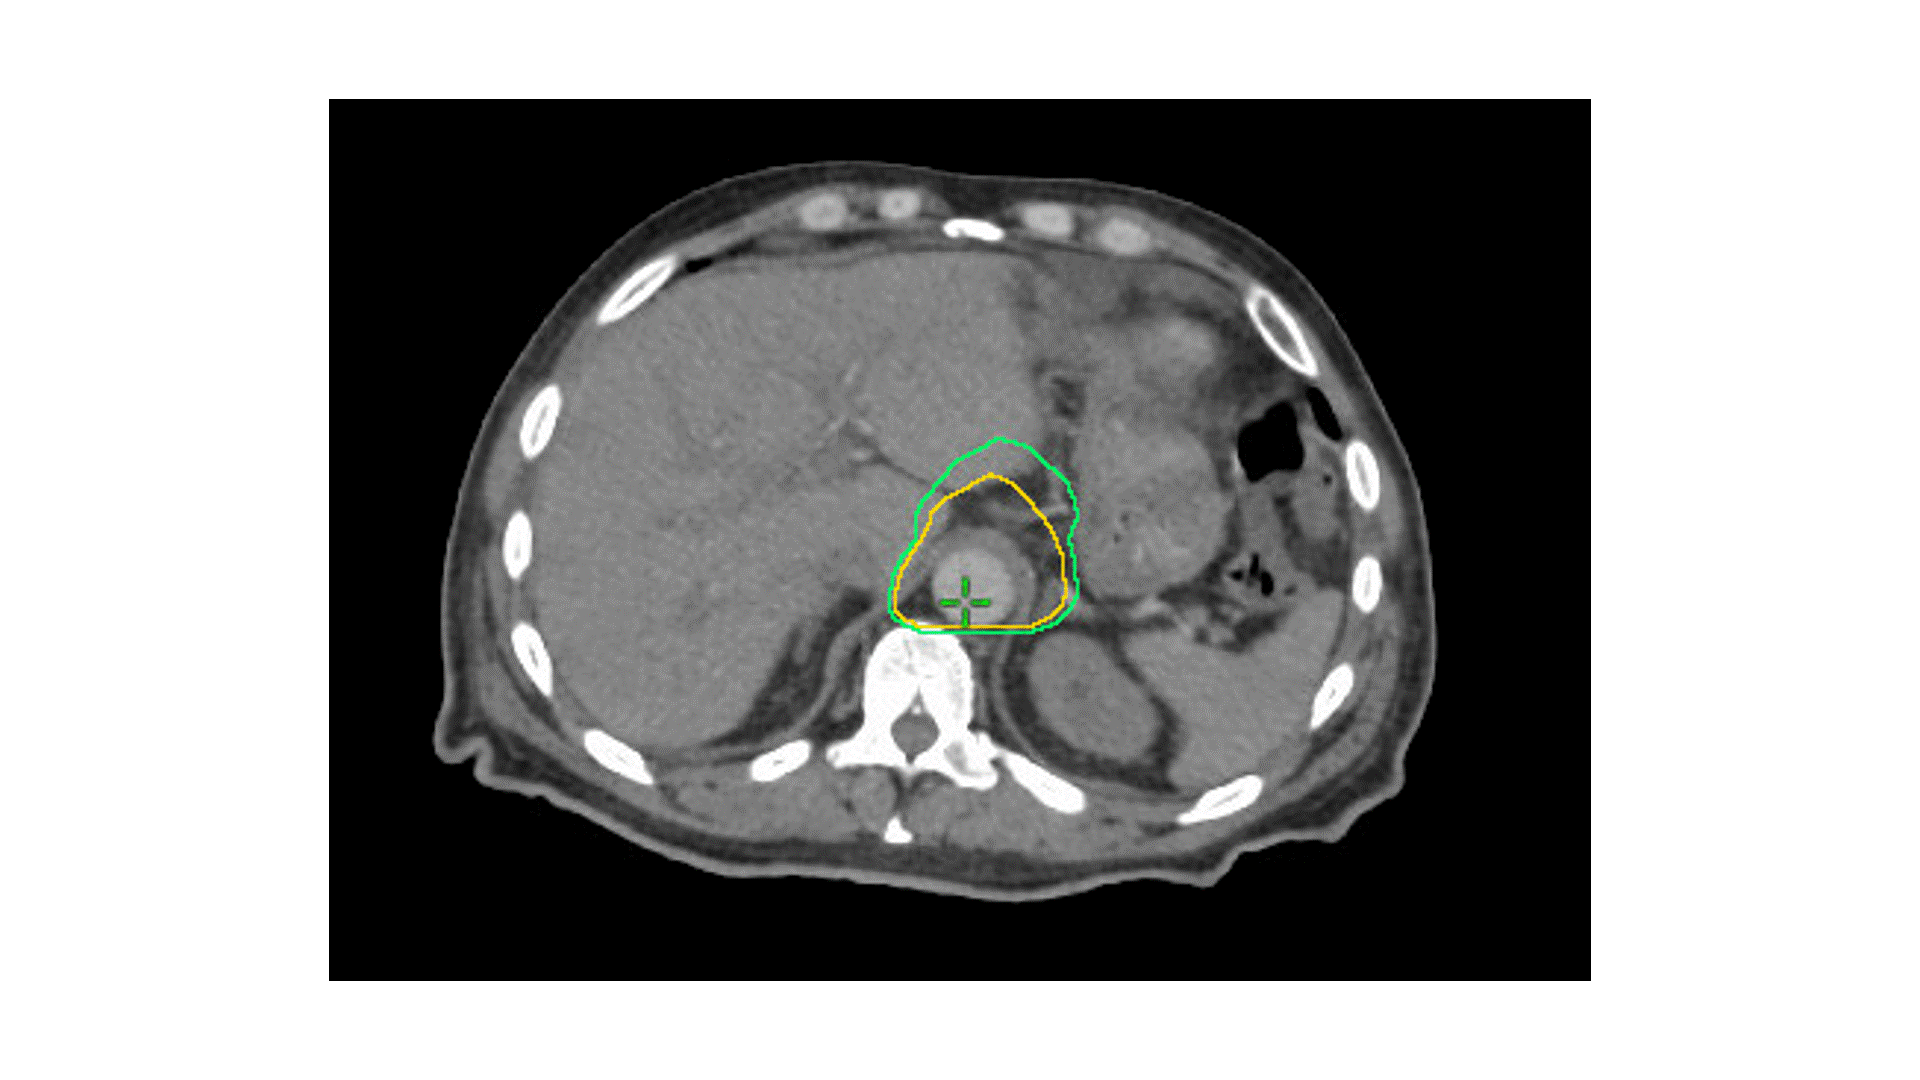

A 56-year-old female with clinical T2N0M0 adenocarcinoma of the head of the pancreas underwent pancreatic resection. Preop CA 19-9 was 153. Final pathology revealed pT2N0 disease with PNI. Negative margins. Postop CA 19-9 was 49.

Which clinical target volume contours are the most appropriate?